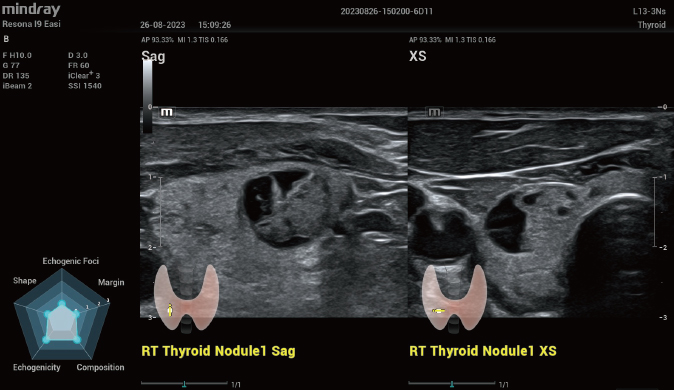

- Smart Thyroid: Avaliação TI-RADS automática, classificando nódulos tireoidianos com maior precisão.